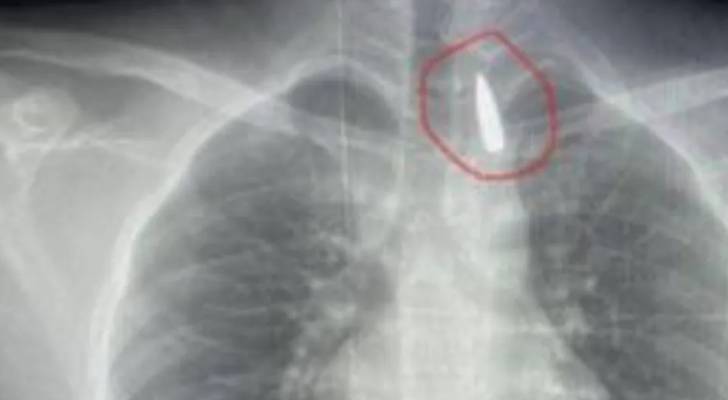

وتمثلت العملية، التي وصفت بـ"بالغة الخطورة"، في استخراج مقذوف ناري كان قد استقر في القفص الصدري على مقربة شديدة من الشريان الأورطي.

وأشار إلى أن المريض، وهو أحد المصابين القادمين من قطاع غزة، كان قد تعرض لإصابة بطلق ناري منذ فترة، استقر المقذوف على إثرها داخل تجويف القفص الصدري.

وأكد "عبد الله" أن خطورة الحالة تكمن في موقع المقذوف، حيث كان مستقرا "قرب الشريان الأورطي"، وهو، كما أوضح البيان، "أكبر وأهم شرايين الجسم والمسؤول عن تغذية جميع الأعضاء الحيوية".

وأضاف أنه على الرغم من دقة الحالة وتعقيدها الشديد، نجح الفريق الطبي في استخراج المقذوف بأمان، بعد عملية جراحية استمرت لعدة ساعات داخل المستشفى الجامعي الجديد.